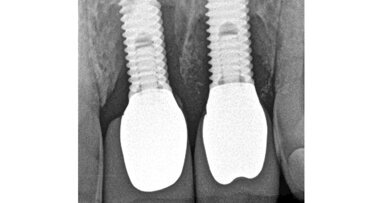

Perforace v dřeňové dutině nebo kořenovém kanálku významně mění prognózu zubu. Oprava perforace pomocí biokompatibilního těsnicího materiálu jako je MTA může ohrožené zuby ušetřit (Mente a spol. 2014) (obr. 3a–e).

Radiolucence v krčkové části špičáku

Aplikace PD MAP White pomocí MAP systému

Původní stav se zaplněnou perforací

Postoperační RTG se zaplněným kanálkem